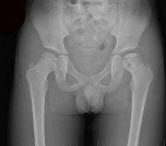

男,根据其正常骨盆影像图像,判断其最可能的年龄()

A.68岁左右

B.58岁左右

C.18岁左右

D.48岁左右

E.28岁左右